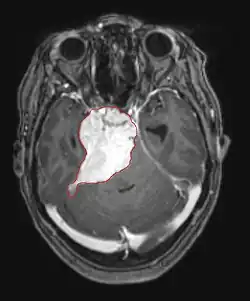

La tomodensitométrie (TDM) et L'imagerie par résonance magnétique (IRM) peuvent détecter efficacement une néoplasie dans le cerveau. L'IRM est plus sensible que la TDM pour identifier les lésions, mais présente des contre- indications pour les patients porteurs de stimulateurs cardiaques, de prothèses incompatibles, de clips métalliques et contre-indications. La TDM reste la méthode de choix pour détecter les calcifications au sein des lésions ou les érosions osseuses de la calotte ou de base du crâne. L'utilisation d' agents de contraste, iodés dans le cas du scanner et paramagnétiques (gadolinium) dans le cas de l'IRM, permet l'acquisition d'informations sur la vascularisation et l'intégrité de la barrière hémato-encéphalique, une meilleure définition de la tumeur tumorale par rapport à l' œdème environnant et à la génération d' hypothèses sur le degré de malignité. L'examen radiologique permet également d'évaluer les effets mécaniques et les modifications importantes des structures cérébrales résultant de la tumeur, telles que l' hydrocéphalie et les hernies, dont les effets peuvent être fatals. Enfin, en préparation à la chirurgie, ce diagnostic peut être utilisé pour déterminer la localisation de la lésion ou l'infiltration de la tumeur dans des zones vitales du cerveau. À cette fin, l'IRM est plus efficace que la tomodensitométrie car elle peut fournir des images en trois dimensions.

Dans le tissu tumoral, en général, la plus grande proportion d'amélioration du contraste est due à la barrière hémato-tumorale particulière qui permet le passage de l'iode (CT) et du gadolinium (IRM) dans l'espace interstitiel extravasculaire intratumoral. Cela augmente le signal (densité ou intensité) de la tumeur. Cependant, des précautions doivent être prises pour s'assurer que l'amélioration du contraste ne différencie pas définitivement la néoplasie de l'œdème péri-lésionnel. En fait, la découverte anatomo-pathologique dans le tissu tumoral infiltrant malin du gliome, comme dans le glioblastome et l'astrocytome anaplasique, montre également au-delà de l'œdème vasogénique causé par la destruction de la barrière hémato-encéphalique par la tumeur. Cette dernière condition clinique est difficilement détectable par imagerie diagnostique.

Sur-L'IRM montre une tumeur intracrânienne comme une lésion massive qui peut devenir plus luminescente après utilisation du produit de contraste. Cependant, il y a toujours une anomalie de signal dans -L'imagerie par résonance magnétique, qui indique la présence d'une néoplasie ou d'un œdème vasogénique. Habituellement, une luminescence accrue (amélioration du contraste) indique une tumeur d'un grade supérieur de malignité. Un anneau de contraste est caractéristique du glioblastome, avec la partie luminescente correspondant à la partie vitale de la tumeur maligne, et la plus foncée - zone hypointense correspondant à une nécrose tissulaire.

Les astrocytomes diffus II apparaissent sur la tomodensitométrie. Grades que les lésions moins intenses. Dans l'imagerie par résonance magnétique préférée, les agents de contraste peuvent ne pas être en mesure de mettre en évidence ces néoplasmes, leur luminescence peut être plus fine et plus faible. Un plus intense peut indiquer des tissus d'anaplasie accrue. Dans la mesure du possible, une biopsie est suggérée pour obtenir des échantillons de la partie anaplasique de la tumeur.